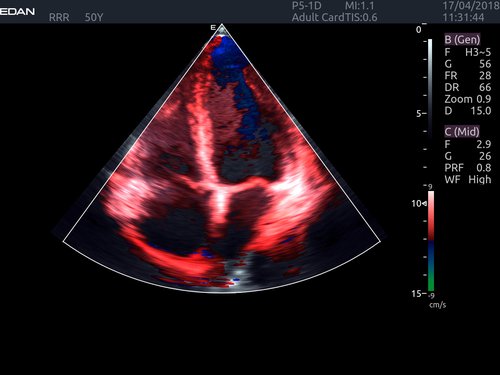

• Features: 3D, 4D, Farb/Doppler, Nadelführung, SW/B-Bild

• Echokardiographie

• Kardiologie